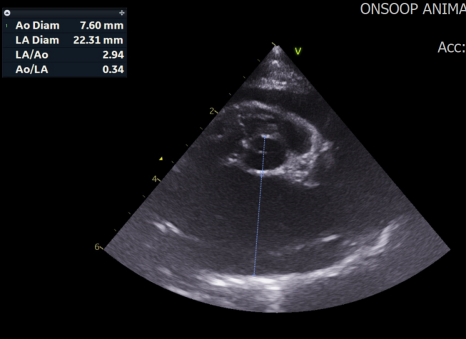

복부 대동맥 초음파 검사 / 출처: 24시온숲동물의료센터

복부 대동맥 초음파 검사

복부 대동맥 분지부와 대퇴동맥 내에서 국소적 혈전(폐색) 이 관찰되었습니다.

이러한 결과는 좌심방압 상승과 혈류의 와류로 인해 혈전이 형성된 전형적인 ATE의 기저 질환 패턴과 일치했습니다.